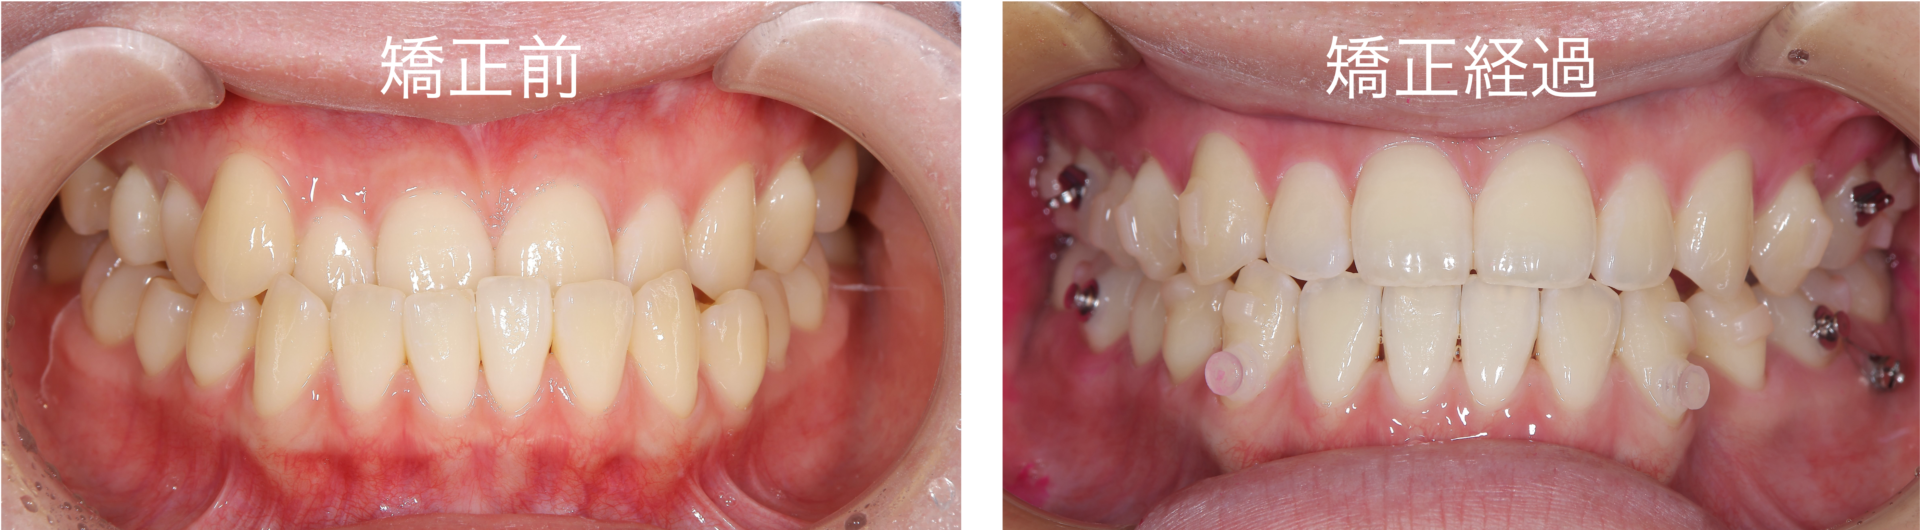

本日は、マウスピース矯正を行い反対咬合(上下の歯の前後関係が反対になっている状態)が改善している患者様に関して報告させていただきます 患者様は20代で、受け口を主訴としてご来院されました骨格的な改善も行うのであれば外科矯正という選択肢もご提示させていただきましたが、お話の結果、歯列矯正で改善を行うことといたしました マウスピース矯正による治療経過になります反 …